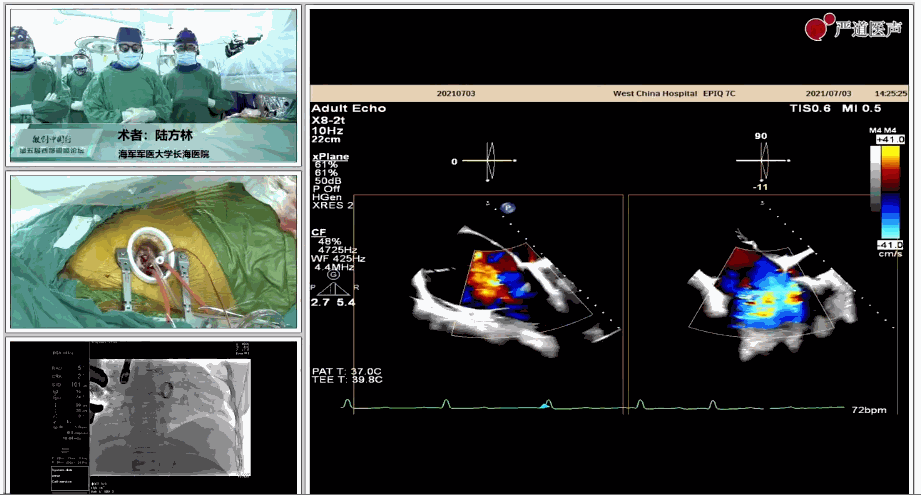

7月3日下午,海軍軍醫(yī)大學(xué)附屬上海長海醫(yī)院心血管外科徐志云、陸方林團(tuán)隊(duì)在論壇中分享了經(jīng)導(dǎo)管三尖瓣置換術(shù)(LuX-Valve®)的手術(shù)直播演示。線下會議由陶涼教授、潘文志教授、喬晨暉教授共同參與討論和臨床分享。

陸方林教授分享的是一例極重度三尖瓣返流的患者采用健世科技(LuX-Valve®)經(jīng)導(dǎo)管三尖瓣置換系統(tǒng)進(jìn)行的手術(shù)直播演示。此例患者為69歲女性,入院前17年行二尖瓣機(jī)械瓣置換術(shù),術(shù)后長期服用華法林抗凝,既往“2型糖尿病”病史5年,“雙下肢水腫”3年。3個月前患者出現(xiàn)腹脹、雙下肢水腫,伴活動后暈厥,伴黃疽、皮膚濕癢、牙齦出血,癥狀持續(xù)加重,遂入院治療。入院后行心臟CT、心臟超聲檢查,提示:“三尖瓣關(guān)閉不全(極重度),二尖瓣置換術(shù)后,心功能III級”。徐志云、陸方林微創(chuàng)三尖瓣置換團(tuán)隊(duì)對該患者的病情進(jìn)行了充分的評估和討論。由于患者有開胸二尖瓣置換手術(shù)史,且病史時間長,同時存在相關(guān)合并癥,傳統(tǒng)外科手術(shù)風(fēng)險(xiǎn)極高(STS評分:8.315%),最終決定采用三尖瓣LuX-Valve®瓣膜系統(tǒng)對患者進(jìn)行治療。

▲術(shù)中食道超聲顯示三尖瓣極重度返流